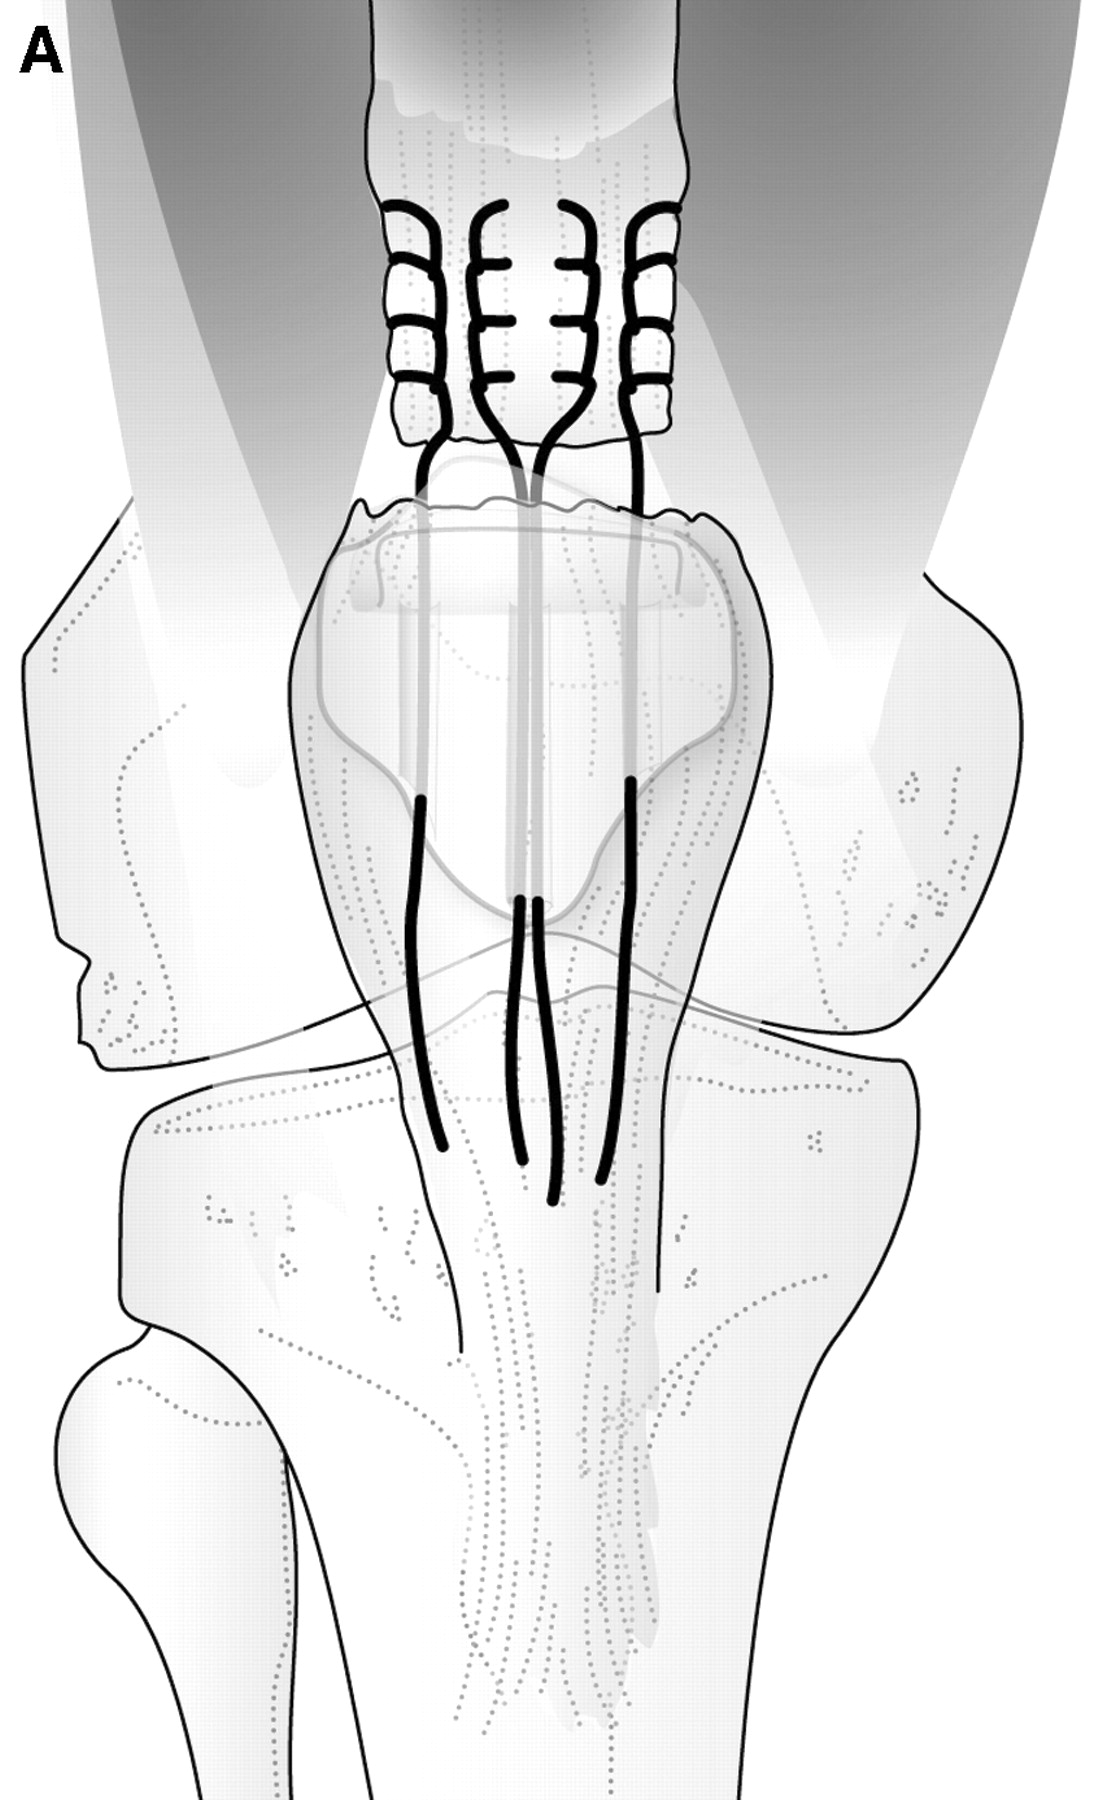

Sutur gennem 3 borekanaler. Brug evt et kanyleret

bor.

Sy med Fiberwire nr 5. Se billede.